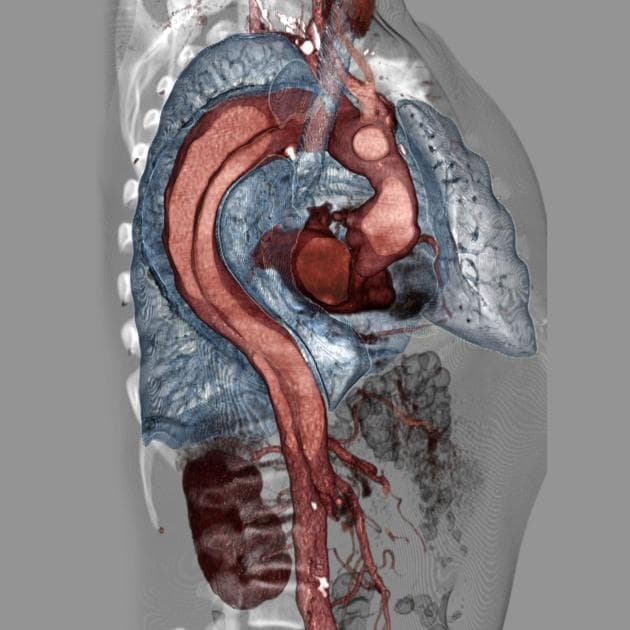

C+ arterial phase

CT•C+ arterial phase•1 / 585

- Một vạt nội mạc bóc tách bắt đầu ở đoạn xa sau khi xuất phát của động mạch dưới đòn trái và lan xuống động mạch chủ ngực xuống và động mạch chủ bụng, cũng như động mạch chậu chung phải.

- Vạt bóc tách này chia lòng động mạch chủ thành một lòng thật nhỏ và một lòng giả lớn hơn (một phần đã bị tắc do huyết khối).

- Giãn dạng phình mạch đoạn động mạch chủ ngực xuống và đoạn động mạch chủ bụng trên thận.

- Các động mạch thân tạng, động mạch mạc treo tràng trên và động mạch thận xuất phát từ lòng thật.

- Không thấy hình ảnh vạt bóc tách lan vào động mạch chậu chung trái.

Phình động mạch chủ bóc tách type B Stanford, type III DeBakey (Stanford B Debakey III dissecting aortic aneurysm).

Trường hợp này là một ví dụ điển hình của bóc tách động mạch chủ type B Stanford, type III DeBakey. Vạt nội mạc bắt đầu sau động mạch dưới đòn trái và lan dọc theo động mạch chủ ngực xuống, động mạch chủ bụng và tới động mạch chậu chung phải. Lòng thật bị chèn ép và nhỏ hơn lòng giả – lòng này một phần đã hình thành huyết khối, một dấu hiệu thường gặp trong các trường hợp bóc tách mạn tính hoặc đang tiến triển. Điều quan trọng là các động mạch tạng (thân tạng, mạc treo tràng trên, thận) đều khởi nguồn từ lòng thật, giúp giảm nguy cơ thiếu máu tưới cơ quan. Tình trạng giãn dạng phình ở đoạn động mạch chủ ngực bụng cho thấy bệnh lý đã tồn tại lâu, làm suy yếu thành mạch và tăng nguy cơ vỡ. Điều trị chủ yếu tập trung vào kiểm soát huyết áp và nhịp tim bằng thuốc, đồng thời cân nhắc can thiệp nội mạch (TEVAR) trong các trường hợp có biến chứng như thiếu máu cơ quan, phình to tiến triển hoặc đau dai dẳng.